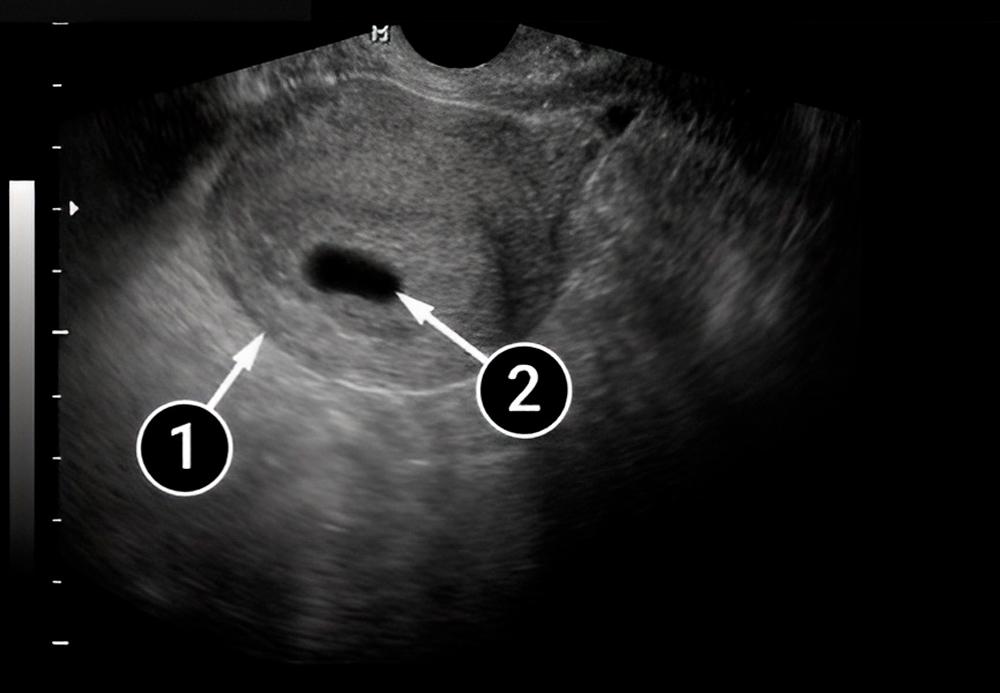

En esta imagen también se pueden ver el útero y el saco amniótico rodeados por el endometrio.

útero

saco amniótico

¡En esta imagen se ve el embrión! Es el pequeño punto blanco dentro del saco amniótico. El endometrio le proporciona nutrientes y sangre al feto.

el embrión